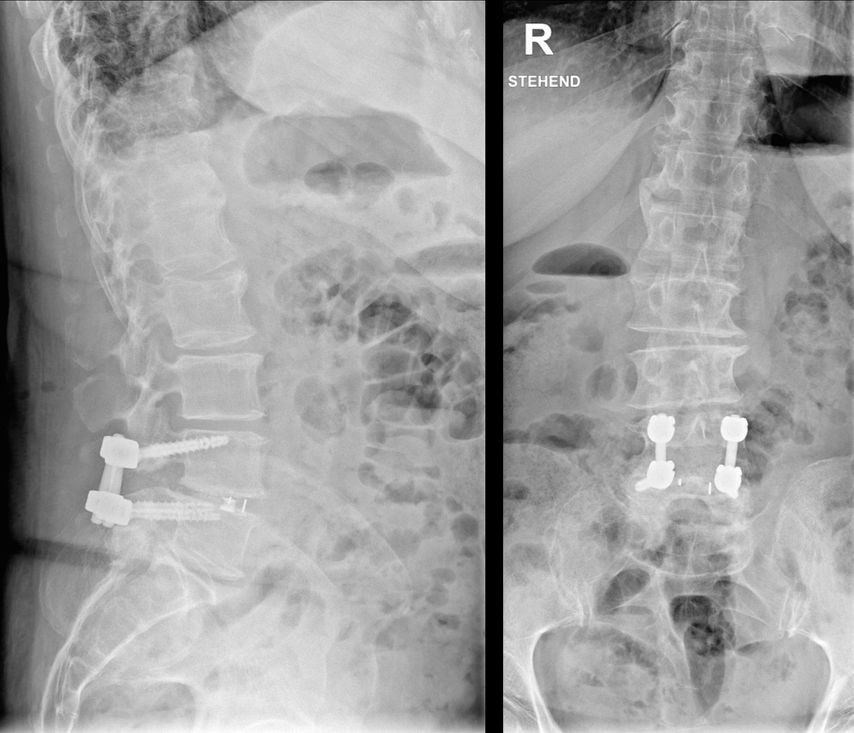

Lässt sich ein Assessment präoperativ zeit- oder strukturbedingt nicht durchführen, können jedoch bereits vorliegende bildgebende Befunde als Informationsquelle genutzt werden. Ein Beispiel ist der MRT-basierte Vertebral Bone Quality Score (VBQ), der im Jahr 2021 von Ehresman et al. beschrieben wurde.9 Die Ermittlung des Wertes wird in Abb. 1 erläutert. Ein anderes Beispiel stellt die Bestimmung der Hounsfield Units (CT-HU) aus einem CT-Scan dar. Ein eindeutiger Cut-off-Wert für den VBQ-Score liegt noch nicht vor, rezente Daten legen jedoch eine Grenze bei ca. 2,4 nahe.10Grundsätzlich besteht eine gute Inter-Rater-Variabilität und die Korrelation mit DEXA-Werten ist gegeben, jedoch kann der VBQ-Score keine DEXA-Messung ersetzen.11 Im Alltag stellt er allerdings eine einfache Möglichkeit dar, Informationen zur Knochendichte zu erlangen, wenn keine rezente DEXA-Messung vorliegt.

Abb. 1: Ermittlung des MRT-basierten Vertebral Bone Quality Score (VBQ) nach Ehresman J et al.9